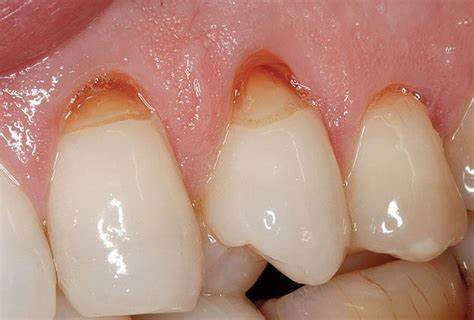

4. Abfraction

Abfraction represents a more recently recognized form of tooth wear, characterized by wedge-shaped lesions at the cervical margin (gumline). The etiology involves:

- Combination with other forms of wear, particularly erosion and abrasion

These lesions typically appear as sharp, V-shaped notches at the cementoenamel junction, often on the facial aspects of teeth under occlusal stress.